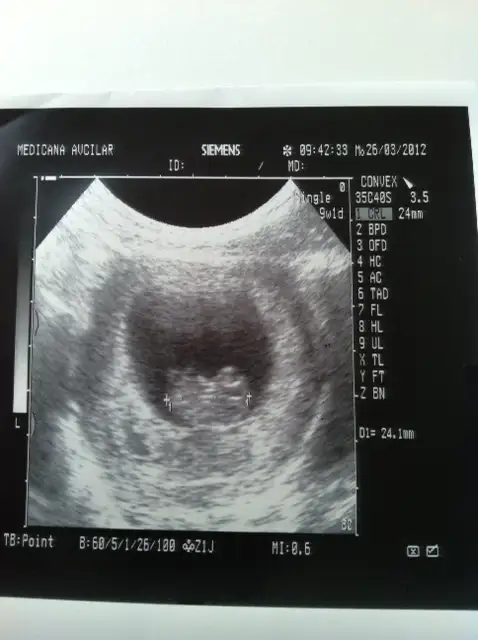

canım ultrason adet tarihime uyumlu bebeklerin ikiside 10 haftanın üzerinde

biri10+1 biri10+5 oldular bugün